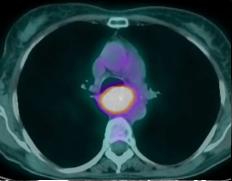

Meme cas : image PET/CT

en coupe axiale a travers tumeur . Tumeur en situ et

extention ganglion hilaire |